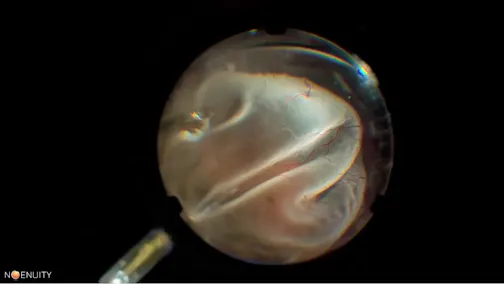

Large Macular Hole

Hua Yan, MD, PhD.